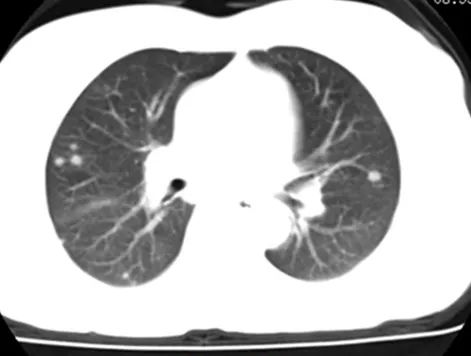

临床研究中NSCLC突变检测有多种取样形式,比如肺活检、淋巴结活检、支气管肺泡灌洗、体腔积液等。

在临床研究中标本的来源也是多种多样。对于呼吸科而言,我们最常用的就是支气管镜,适用于中央型、较大病灶的活检取样;与支气管内超声结合,如EBUS-TBLB,EBUS-TBNA;EBUS-TBNA侵入性更小,准确性可比肩纵隔镜。对于伴胸水患者,胸腔穿刺采集胸水进行细胞学检查。如果有外周型病灶,需经CT引导胸腔皮下细针抽吸,存在一些局限性,可导致气胸风险,对于不良反应、适应症的问题,会有相应的处理方式。如果以上方法均无法实现准确取样、诊断时,考虑使用外科方法活检取样。

经皮肺穿活检术能活检多大结节?

根据病灶在胸部影像学上的表现可设定顺畅的进针轨道,穿刺结节的大小无明显限制,小于1cm的结节,穿刺的假阴性率明显上升。因此,经皮肺穿刺活检依赖于操作者的技术水平、影像科定位及病理科检测的敏感性,建议操作科室(呼吸科或肿瘤科等)、影像科及病理科多学科联合制定。